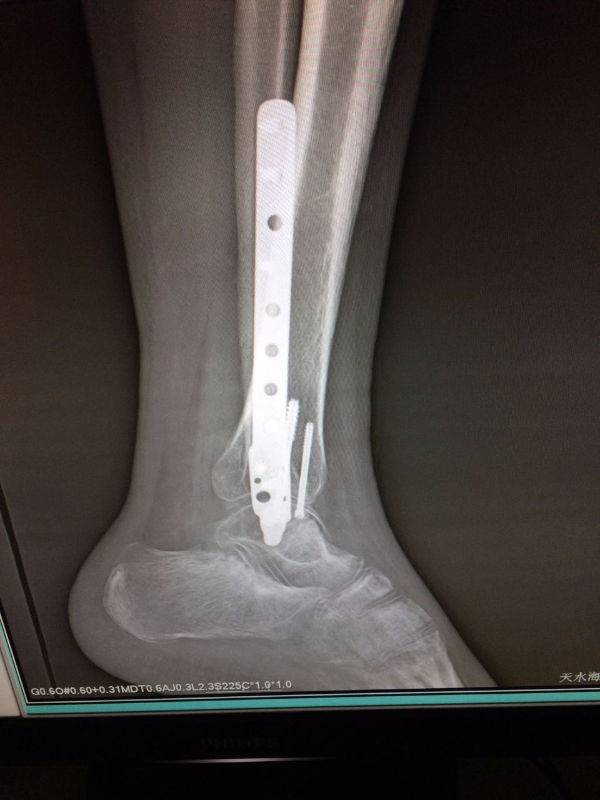

手术非常好,顺便请教一下。患者.男,25岁,右腓骨下段及内踝骨折,切开复位内固定术后120天,外踝部钢板外露,半月前行扩创缝合,目前仍未完全愈合,伴少量渗出,踝关节功能僵硬。请教治疗方案。谢谢

mmexport1496478319278.jpg